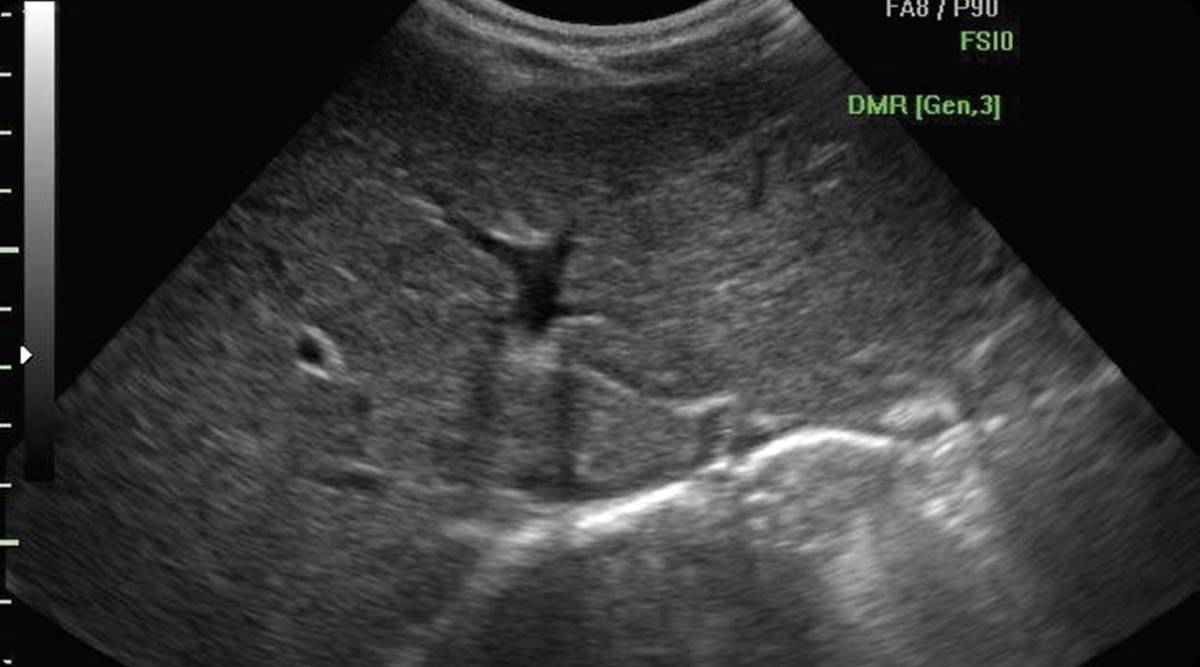

Вот так выглядит печень на УЗИ